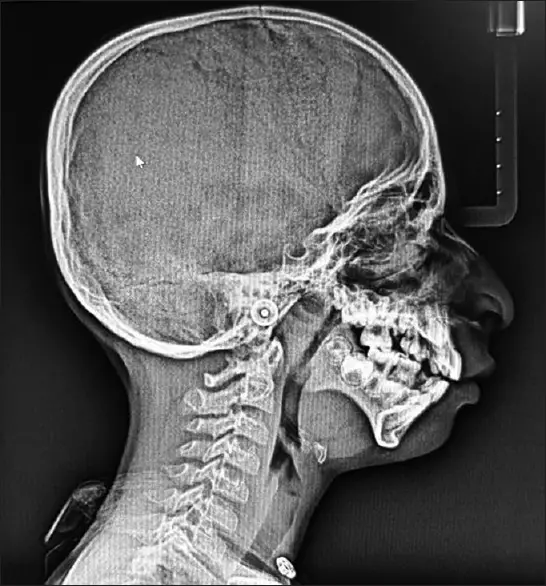

پس از یک سری معاینات، مشاوره و آزمایش ژنتیک، متخصصان پزشکی در نهایت به یک تشخیص قطعی رسیدند؛ سندرم تریچر کالینز (TCS). این اختلال ژنتیکی نادر بر رشد استخوانها و بافتهای صورت در طول رشد جنین تأثیر میگذارد و منجر به ناهنجاریهای صورت و اختلالات شنوایی میشود. اعتقاد بر این است که ناشی از جهش در ژنهای TCOF1، POLR1C یا POLR1D است، اگرچه در برخی موارد، علت ناشناخته باقی میماند.

سندرم تریچر-کالینز که به نام دیسوستوز فک پایین نیز شناخته می شود، یک اختلال ژنتیکی بسیار نادر است که تقریباً از هر 50000 تولد زنده 1 نفر را تحت تأثیر قرار می دهد. اگرچه شدت این بیماری در بین افراد متفاوت است، ویژگی های مشترک عبارتند از: TCS اساساً استخوانها و بافتهای صورت را تحت تأثیر قرار میدهد و در نتیجه استخوانهای گونه، فک و چانه رشد نکرده است. در نتیجه، افراد مبتلا اغلب ظاهری متمایز دارند که با چشمهای متمایل به پایین، گوشهای کوچک و بد شکل و چانه عقبرفته مشخص میشود.